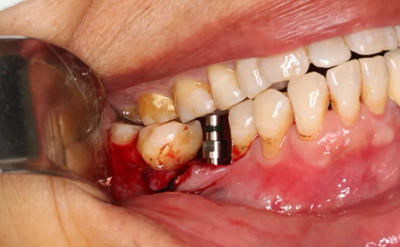

11、常規(guī)植入WEGO種植體一顆

牙槽嵴頂水平切口,翻瓣,牙槽嵴近中較遠(yuǎn)中豐滿(mǎn)。

(攝于2017年4月14日)